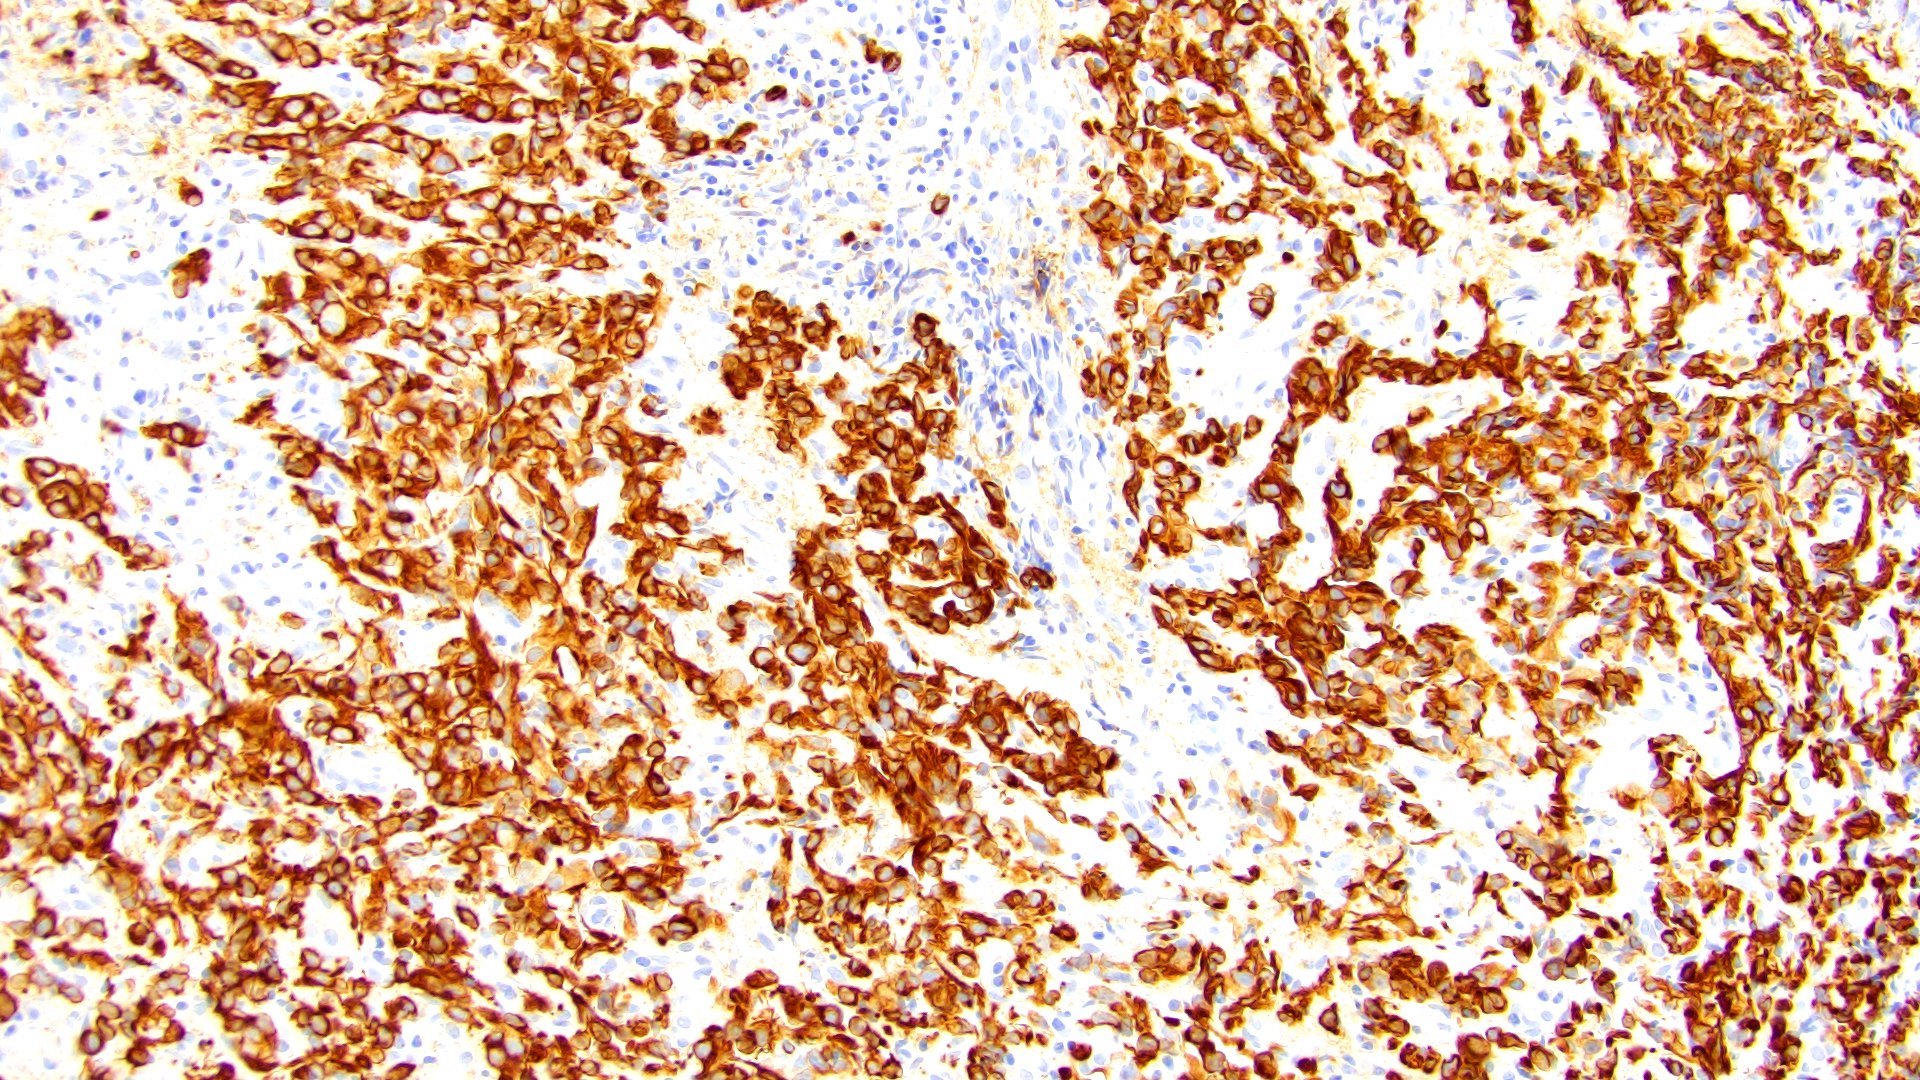

Microscopic (histologic) images

Contributed by Timothy Isaac Miller, M.D., M.A., Nicole K. Andeen, M.D. and Maria Tretiakova, M.D., Ph.D.

Contributed by Lisa Han, M.D. and Ricardo Lastra, M.D. (Case #510)

Positive stains

- Pancytokeratin

- GATA3 (80 - 96% sensitive) (Hum Pathol 2019;90:27, Am J Clin Pathol 2017;147:500, Arch Pathol Lab Med 2019;143:1562)

- CD138 (~83% sensitive) (Hum Pathol 2019;90:27, Int J Clin Exp Pathol 2012;5:601)

- CK7 (85 - 89%) (Hum Pathol 2019;90:27, Am J Clin Pathol 2017;147:500)

- CK20 (76 - 77%) (Hum Pathol 2019;90:27, Am J Clin Pathol 2017;147:500)

- Uroplakin II (33 - 69%) (Hum Pathol 2019;90:27, Am J Clin Pathol 2017;147:500, Am J Surg Pathol 2017;41:1570)